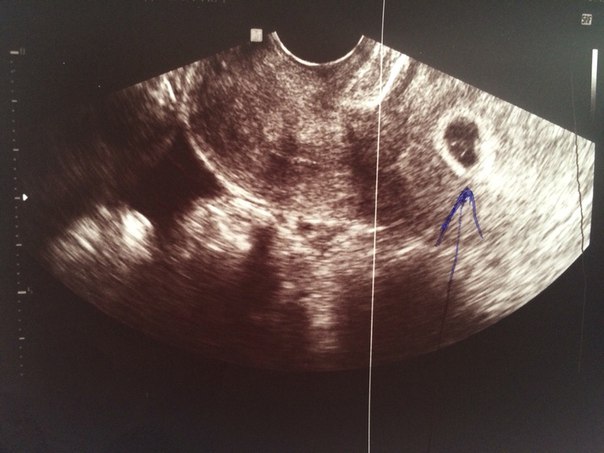

Вот и наше первое фото, сделанное на УЗИ на сроке 4-5 недель.

На 5-ой неделе начали беспокоить спазмы ниже живота. Немедленно пошла к врачу. Она направила на УЗИ. Хоть и маленькая но УГРОЗА есть сказала она. Переживаю, делаю все чтобы малыш был в покое. Доктор назначила "Лютеина" (прогестерон). Это же гормооон, ужаснулась я. Но потом прочитала аннотацию данного препарата, и успокоилась. Так как, как раз таки во время угрозы выкидыша его назначают врачи. Пью по назначению. Стоит заметить что еще никогда я не относилась к своему здоровью так бережно как во время беременности.